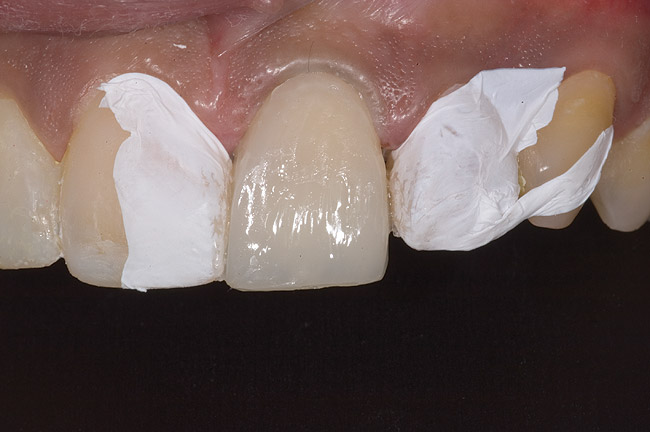

Figure 9: Tooth No. 9 minimally prepared for resin layering on the labial surface.

Figure 9

During the next appointment, a palatal index of the approved provisional was fabricated with putty silicone. This enabled the clinician to precisely build the lingual surfaces and incisal edges of teeth Nos. 6 through 11. The provisional mock-up resin on No. 9 was removed, and the underlying labial tooth was roughened with an abrasive diamond bur. No tooth structure was removed from the palatal surface, and unsupported enamel was rounded off from the labial. An ultrathin dry cord was placed in the gingival sulcus on No. 9 (Figure 9 and Figure 10). Teflon tape was used to isolate No. 9 from adjacent teeth. Then 37% phosphoric acid was used to totally etch the labial surface for 10 seconds and the palatal surfaces on No. 9 for 5 seconds. Single bond was applied and spread uniformly across the tooth and light-cured for 20 seconds.